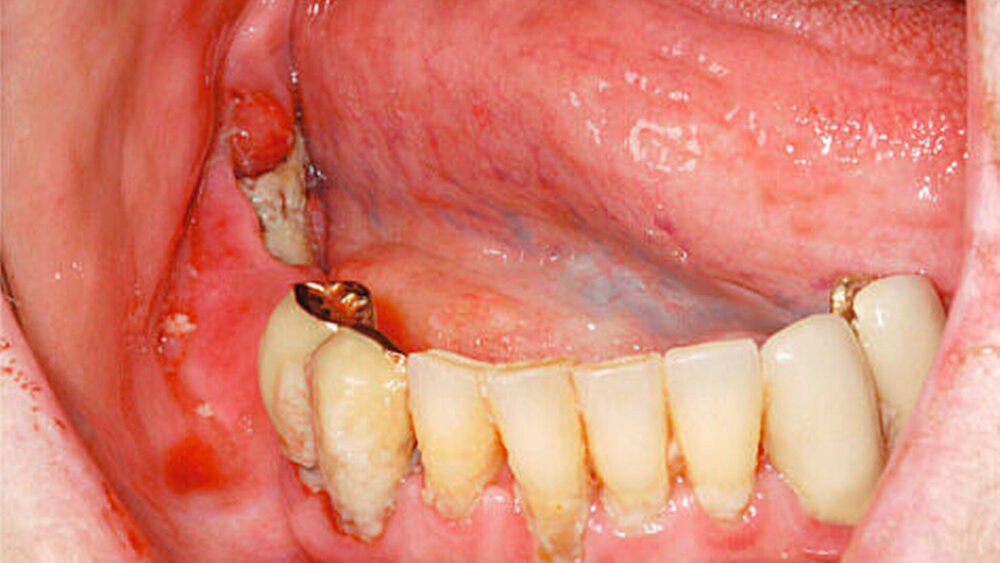

Die akute (infektiöse) OM geht nach vier Wochen per definitionem in eine sekundär chronische OM über (Abbildungen 1 und 2) [Marx, 1991] und beschreibt daher eigentlich die gleiche Entität zu unterschiedlichen Zeitpunkten und zu unterschiedlichen Stadien.

Typisch für die akute Osteomyelitis sind neben den starken Schmerzen die Abszess- und die Pusbildung, wie auch erhöhte Entzündungswerte. Ein reduzierter Allgemeinzustand, Fieber, Foetor, Zahnlockerungen, eine Hypästhesie sowie eine Mundöffnungseinschränkung können zusätzlich vorliegen.

Neben den bekannten Bisphosphonaten werden zunehmend Fälle von Kiefernekrosen auch durch Denosumab, einen RANKL-Antagonisten, beobachtet. Deswegen sollte speziell auch nach den Medikamenten Prolia©und XGeva©vor oralchirurgischen Eingriffen gefragt werden. Während Prolia©in der Osteoporosetherapie Anwendung findet, wird XGeva©bei Prostata- und Mammakarzinompatienten subkutan verabreicht und hat speziell auch bei Nierenfunktionsstörungen seine Indikationen. Die Halbwertszeit von Bisphosphonaten beträgt bis zu zehn Jahren, die von Denosumab in der Regel zwischen 80 und 120 Tagen [Ruggiero, 2013]. In direkten Vergleichsstudien bei onkologischen Patienten werden etwas mehr gehäuft Nekrosen durch Denosumab als durch Zoledronat (Aminobisphosphonat) festgestellt. Die Erfolge einer definitiven Heilung waren jedoch bei den Denosumabnekrosen scheinbar besser [Saad et al., 2012; Van Wyngaert et al., 2011]. Als Hauptursachen einer Kiefernekrose sind bei beiden Präparaten nach wie vor Zahnextraktionen zu nennen. Das zweitgrößte Risiko durch Prothesendruckstellen wird jedoch häufig unterschätzt (Abbildungen 5 und 6) [Hoefert, 2012].